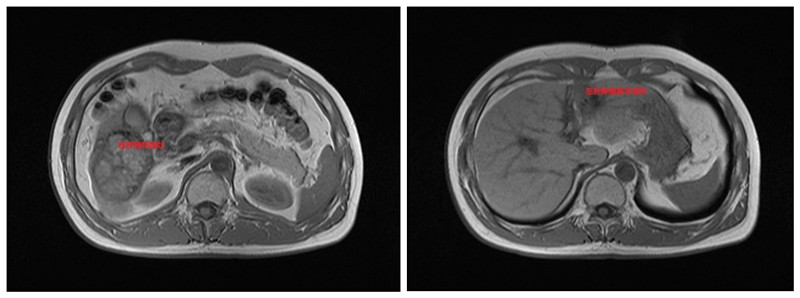

在科室主任沈永奇主任医师的带领下,肿瘤科团队对患者进行个体化的处置:先予HAIC术(经皮肝动脉置管持续灌注化疗术),待肿瘤缩小后再行TACE术(经皮肝动脉置管灌注化疗栓塞术),残余病灶予适形调强放疗。到2024年6月患者复查影像学显示肿瘤明显缩小,“右肝肿物最大径线约76mm×61mm、左肝肿物最大径线约21mm×16mm”,AFP 5.62 ng/ml。

经我院再次肝癌MDT讨论,认为患者肝脏肿瘤降期成功,可以进行手术切除。2024年9月27日,肿瘤科团队为患者成功行了“肝癌根治性切除术”,手术顺利,肿瘤完整切除,患者获得新生。目前已康复出院。